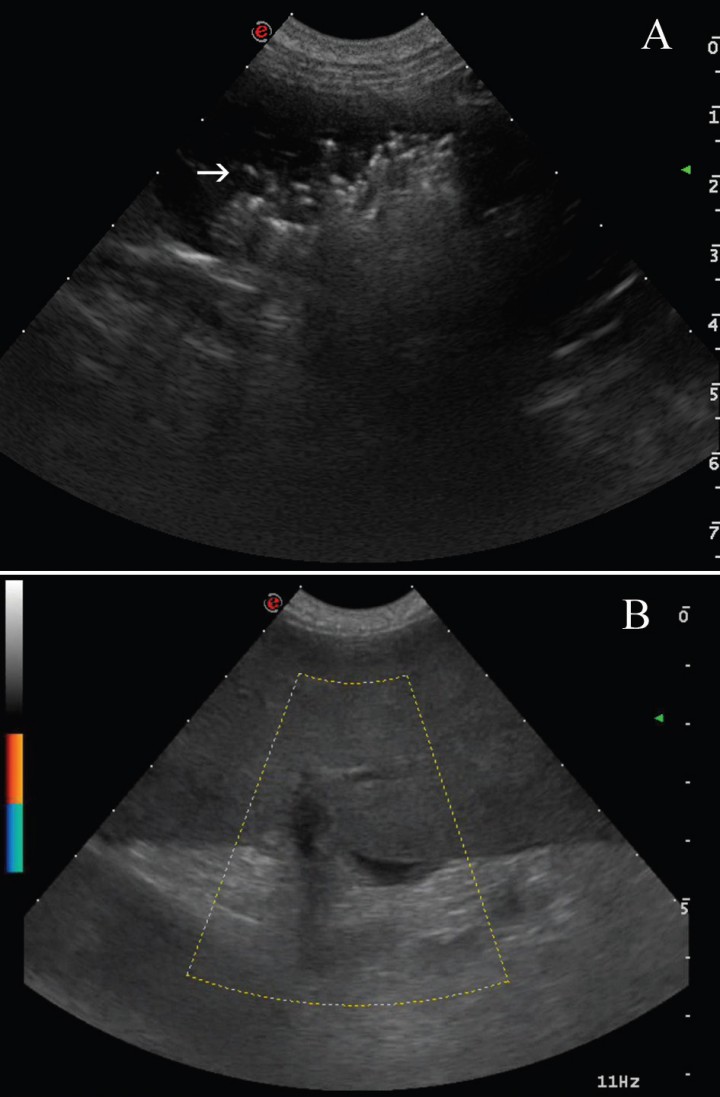

Se realizó un examen ecográfico de la cavidad abdominal observándose el bazo aumentado de tamaño e hipoecogénico, con áreas hiperecogénicas asociadas al artefacto de reverberación sugiriendo la presencia de gas intraparenquimatoso (Fig. 3A). El estudio con Doppler-color, reveló la ausencia de vascularización en el hilio esplénico y en el parénquima (Fig. 3B). También se visualizó líquido libre. Los hallazgos ecográficos corroboraron el diagnóstico presuntivo de torsión esplénica enfisematosa.

<p>Imagen ecográfica del bazo. (A) Se visualiza hipoecogénico con áreas hiperecogénicas asociadas al artefacto de reverberación sugiriendo la presencia de gas intraparenquimatoso. (B) Al aplicar el Doppler-color, no se aprecia vascularización.</p>

Imagen ecográfica del bazo. (A) Se visualiza hipoecogénico con áreas hiperecogénicas asociadas al artefacto de reverberación sugiriendo la presencia de gas intraparenquimatoso. (B) Al aplicar el Doppler-color, no se aprecia vascularización.

En la evaluación ecográfica, se evidencia esplenomegalia con áreas difusas hipo o anecógenas debido a los vasos sinusoides congestivos, y múltiples líneas ecogénicas procedentes de los vasos dilatados, imagen descrita como un patrón típico de cielo estrellado.[ Patsikas MN, Rallis T, Kladakis SE et al.: Computed tomography diagnosis of isolated splenic torsion in a dog. Vet Radiol & Ultrasound 2001, 42: 235-237. [PubMed] , Haller JM, Fabiani MH; What is your diagnosis? Ischemia of the spleen. J Am Vet Med Assoc 2013, 242: 1481-1483. [PubMed] , Jaeger GH, Maher E, Simmons T: What is your diagnosis? Splenic torsion J Am Vet Med Assoc 2006, 229, 501-502. [PubMed] ] En los casos que exista enfisema esplénico, además se visualizarán pequeños puntos ecogénicos con reverberación en el parénquima esplénico de forma focal o difusa.[ Simeonova G, Simeonov R, Roussenov A: Uncommon cause of acute abdomen in a dog: Torsion of the spleen – Case report and review. Trakia J Sc 2007, 5: 3-4. ] Si se utiliza la ecografía Doppler, no se detectará el flujo sanguíneo de las venas esplénicas.[ Patsikas MN, Rallis T, Kladakis SE et al.: Computed tomography diagnosis of isolated splenic torsion in a dog. Vet Radiol & Ultrasound 2001, 42: 235-237. [PubMed] , Simeonova G, Simeonov R, Roussenov A: Uncommon cause of acute abdomen in a dog: Torsion of the spleen – Case report and review. Trakia J Sc 2007, 5: 3-4. , Haller JM, Fabiani MH; What is your diagnosis? Ischemia of the spleen. J Am Vet Med Assoc 2013, 242: 1481-1483. [PubMed] , Jaeger GH, Maher E, Simmons T: What is your diagnosis? Splenic torsion J Am Vet Med Assoc 2006, 229, 501-502. [PubMed] ] En nuestro caso los hallazgos ecográficos coincidieron con los descritos anteriormente. Aunque la ecografía es una técnica no invasiva y precisa, también se puede utilizar la tomografía computarizada, observándose esplenomegalia, el pedículo esplénico en forma de espiral y el bazo en forma de C en torsiones mayores a 180º.[ Simeonova G, Simeonov R, Roussenov A: Uncommon cause of acute abdomen in a dog: Torsion of the spleen – Case report and review. Trakia J Sc 2007, 5: 3-4. ]